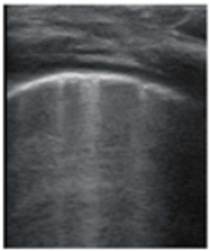

Figure 3. The lung ultrasound showed (a) sparse B-lines with small zones of pleural irregularities corresponding to a LUSS = 1; (b) confluent B-lines with aspect of ‘white-lung ‘corresponding to LUSS = 2. - Confluent or coalescent B-lines (Figure 3b)—57.89%;

- ‘White-lung’ (Figure 3b)—36.84%;